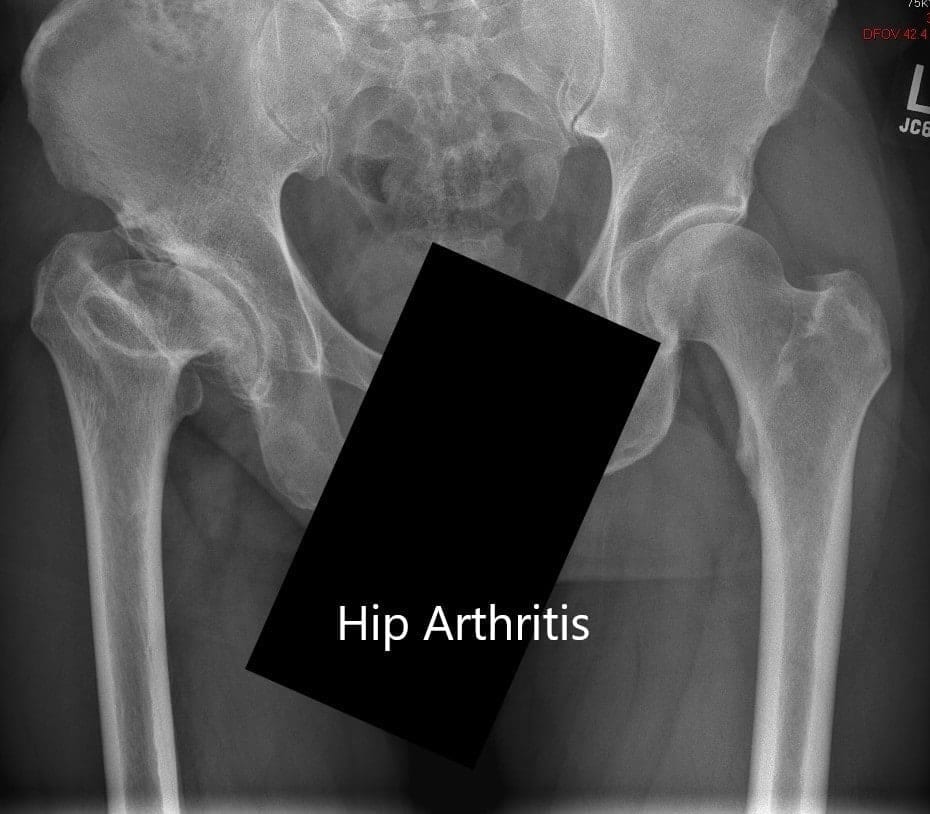

Radiografía preoperatoria que muestra la vista AP de la pelvis con ambas articulaciones de la cadera

Vistas AP y laterales de la articulación de la cadera derecha

Las imágenes revelaron una cabeza femoral derecha marcadamente deformada que afectó el cuello femoral. Hubo cambios degenerativos severos en la cadera derecha.